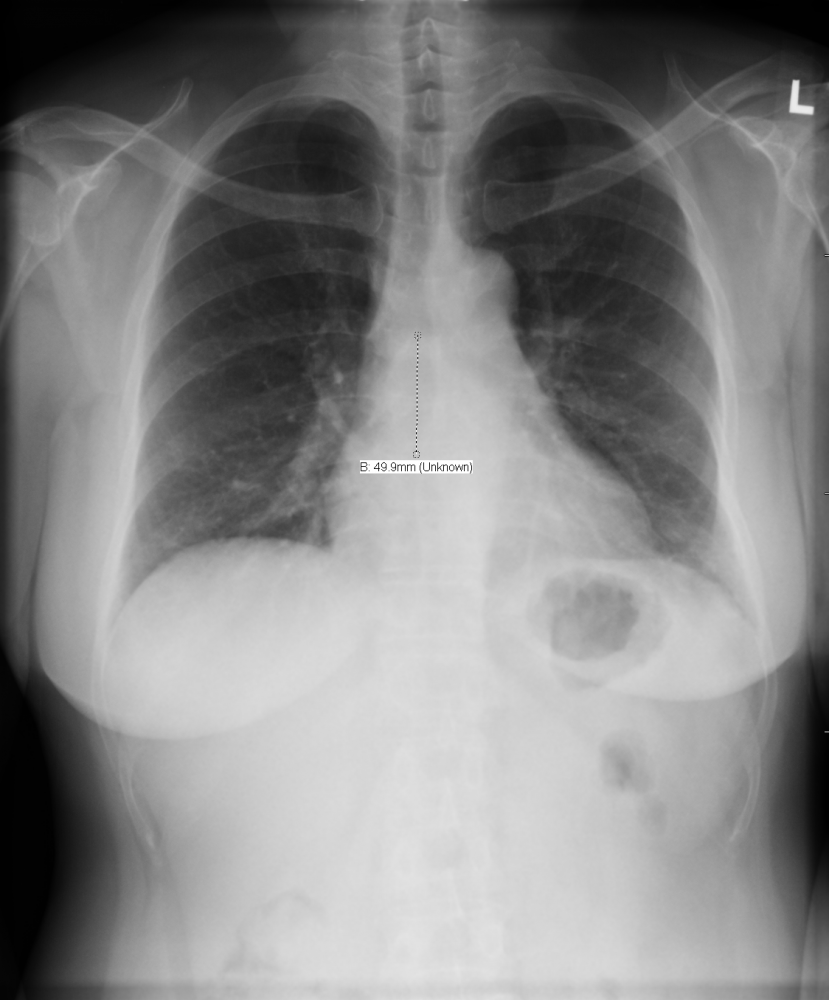

Figure - 01

CXR Sweet Spot™ Box Measurements |